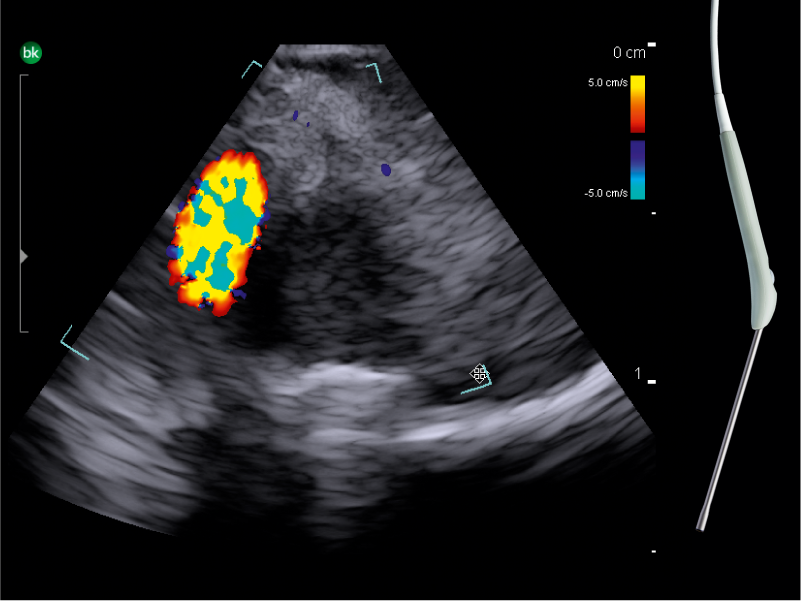

DIGITAL INTEGRATION WITH BRAINLAB

Surgical Visualization and Guidance’s active imaging solutions combined with Brainlab Navigation can be a powerful tool to provide critical information that helps neurosurgeons navigate procedures.

Brainlab Ultrasound Navigation Software provides updated images for navigation and enables real-time overlay of ultrasound imaging on preoperative MRI/CT, providing immediate information about brain shift. The digital transmission ensures no loss of ultrasound image quality.